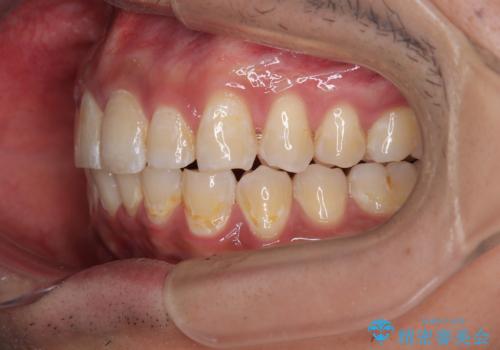

深い咬み合わせと前歯のデコボコ ワイヤー装置での抜歯矯正

- 深い咬み合わせと前歯のデコボコを改善したいとのことで来院された患者様です。

口元の突出感はないものの、上顎前歯のデコボコが著しく、右側の咬み合わせがずれていたため、上顎右側第一小臼歯1本を抜歯することとしました。

咬合力が非常に強く、抜歯したスペースがなかなか閉じないであろうことは予想できましたが、思っていた以上に期間がかかりました。

前歯のすり減りも著しかったため、仕上げの位置の調整にも期間を要しました。